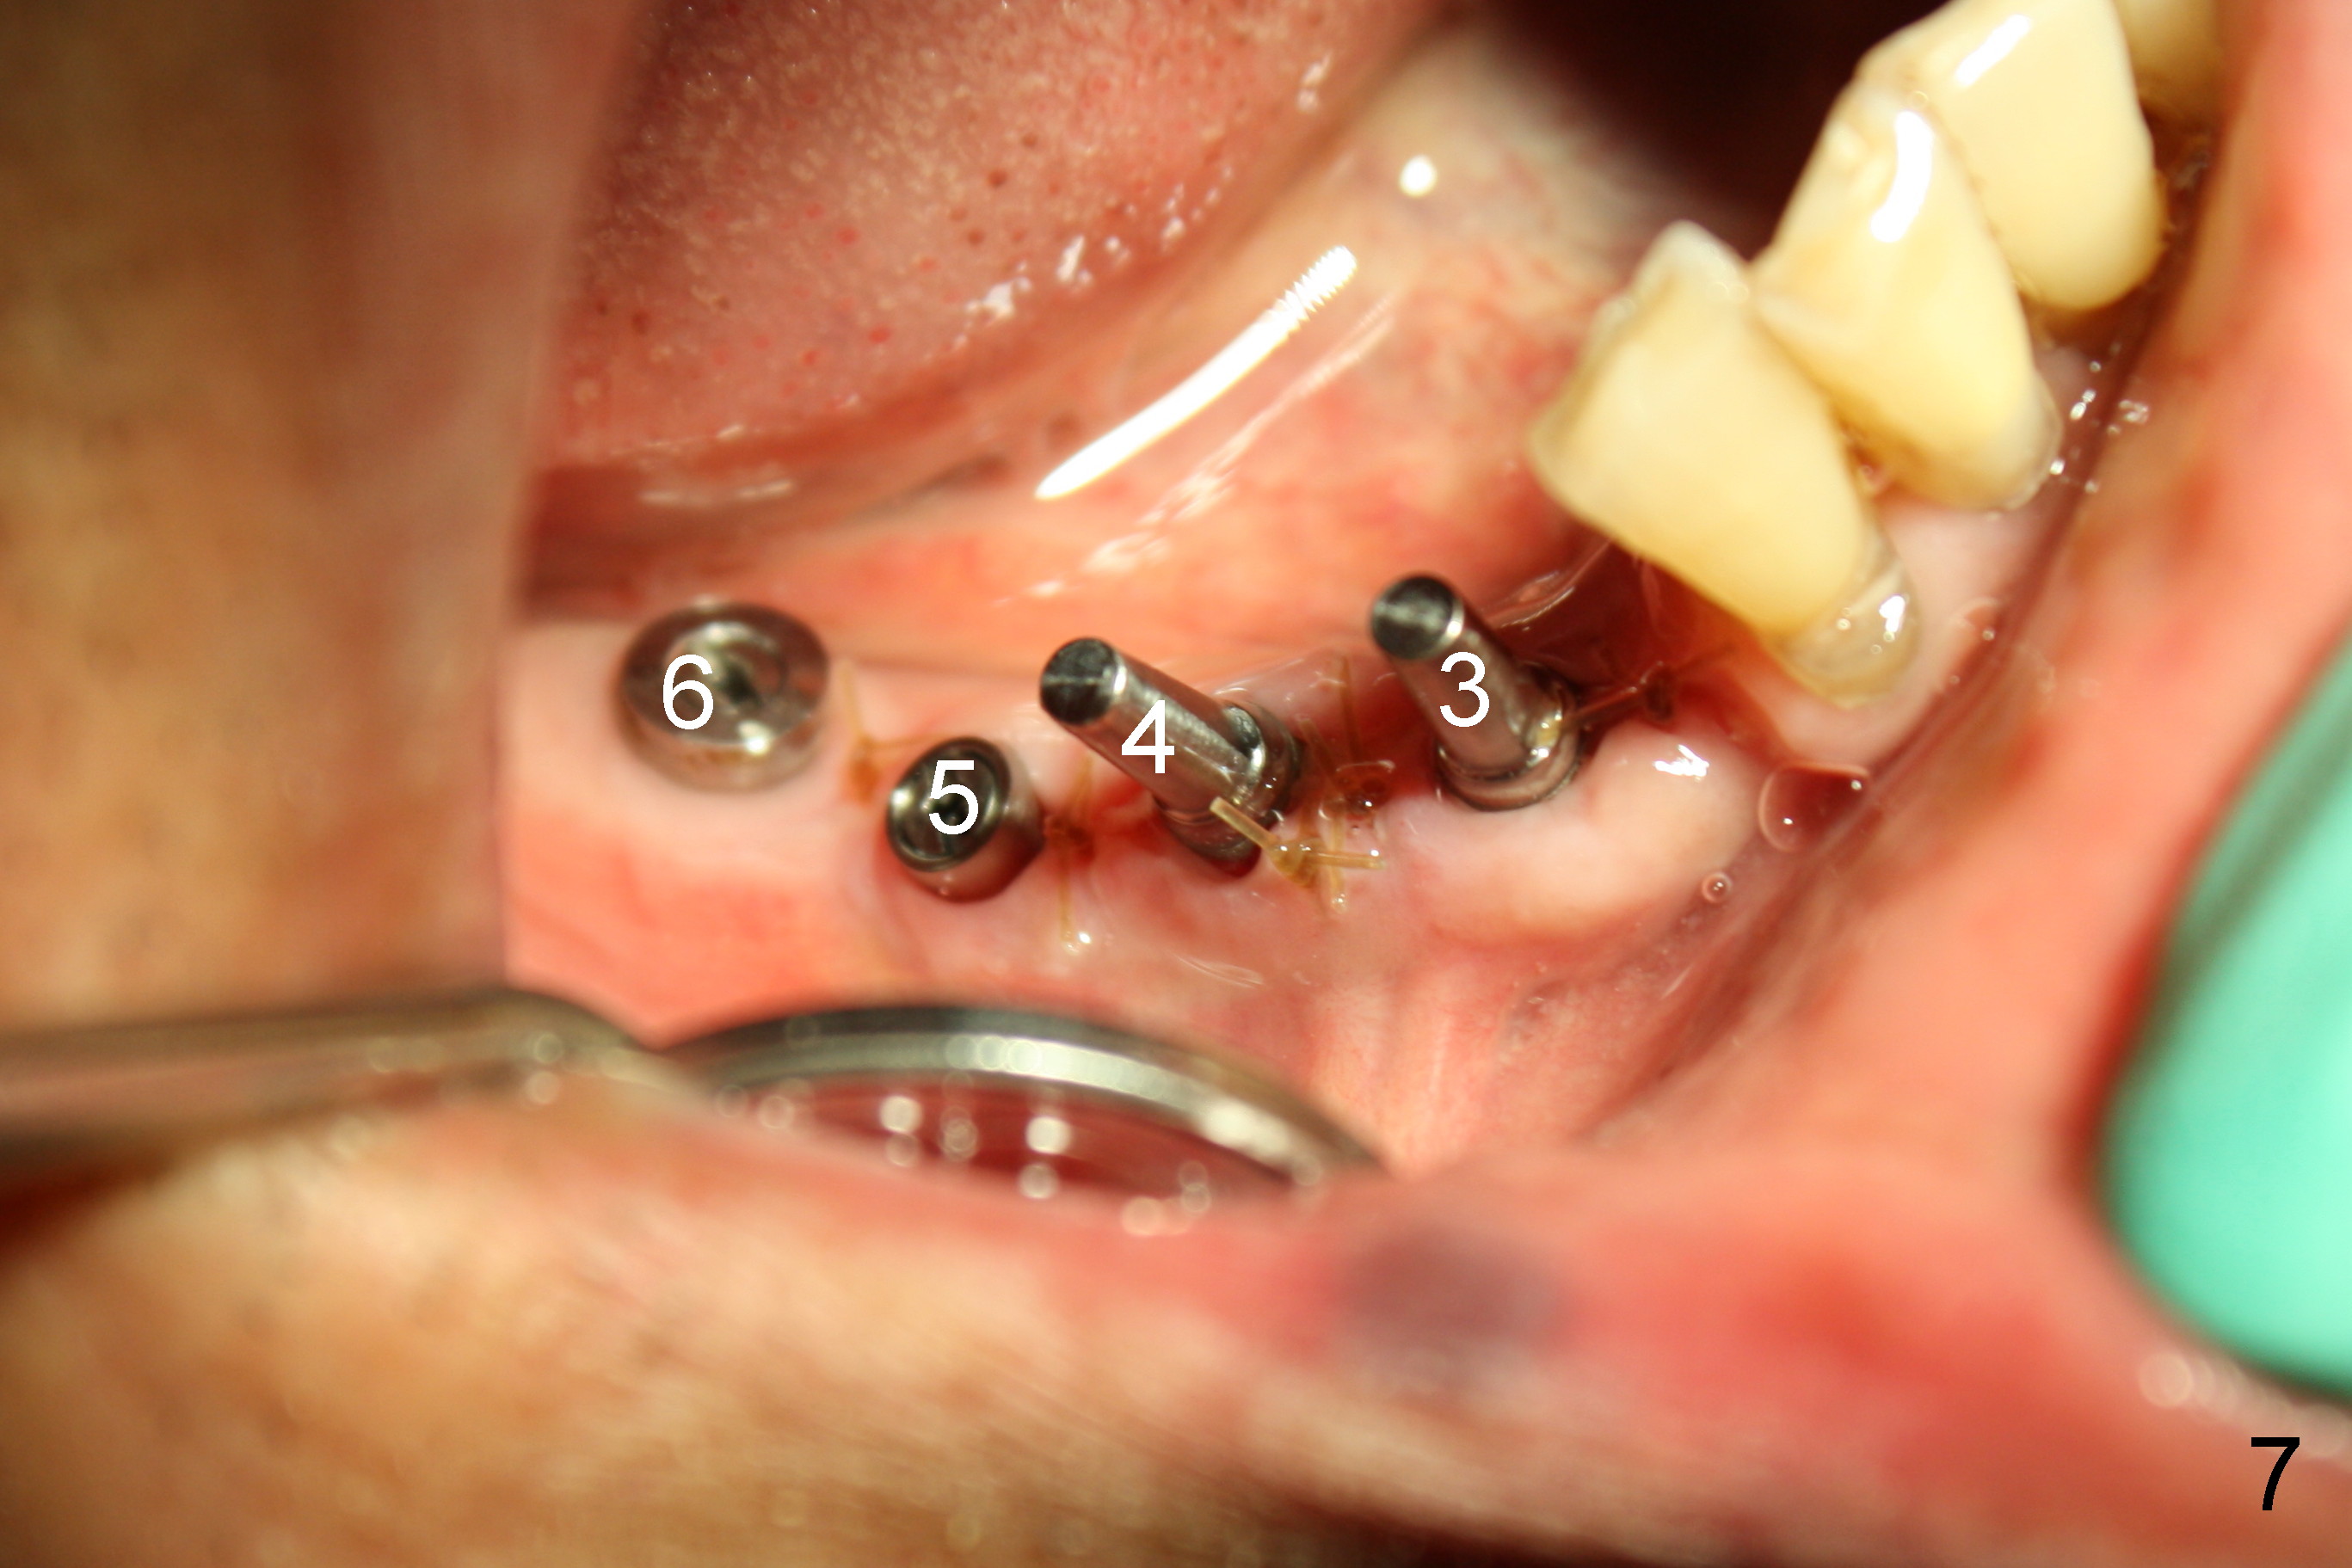

The lower right bridge (from canine (Fig.2: 3) to 1st molar (Fig.1: 6)) fails while a 77-year-old man is undergoing chemotherapy for urinary bladder cancer. The abutments of the bridge are extracted without plan for implants (Fig.4). Four months later, the patient returns for implants (Fig.3), but the ridge is narrow (Fig.5). While 2 of 3x14 mm 1-piece implant are placed at the canine and 1st bicuspid sites, 2 piece ones at the 2nd bicuspid and 1st molar sites (Fig.6: 3.5x11 mm, 5x14 mm). Soft (Fig.7-10) and hard (Fig.11) tissues heal 1 week (Fig.7) and 4 months (Fig.8-11). There is minimal bone resorption 1 year 7 months post cementation (Fig.12,13, non-splinting). It appears that narrow diameter implants are a valid solution to narrow ridge at the sites of the lower canine and premolar. As long as there are enough implants for function, the crowns are not necessary to be splinted. Surprisingly, the patient starts flossing after implant restoration. Retrospectively an immediate provisional bridge should have been fabricated.